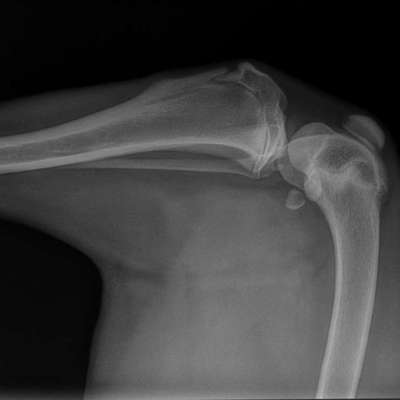

Vorab: die Qualität des Bildes hier auf dem Handy reicht nicht für eine valide Beurteilung. Röntgenbilder werden an speziellen Monitoren beurteilt und das nicht ohne Grund.

Was sehen wir?

In Grün eingekreist die beiden Sesambeine. Oben die Patella und unten die beiden Sesambeine vom M. gastrocnemi (Kniekehlmuskel). Die gehören beide da hin.

In Gelb die Wachstumsfuge des Schienbeins.

In Rot ist 1. das, was ich für die Knochenhautentzündung halten würde am Oberschenkel.

Rot 2 könnte man tatsächlich als Gelenk-Chip interpretieren, allerdings ist die Aufnahme etwas verkippt, das mag also auch an der Überlagerung liegen.

Oben wo der Kringel ist. Da ist der Knochen aufgetrieben. Ist ja eine andere Röntgenperspektive und anderes Gelenk.